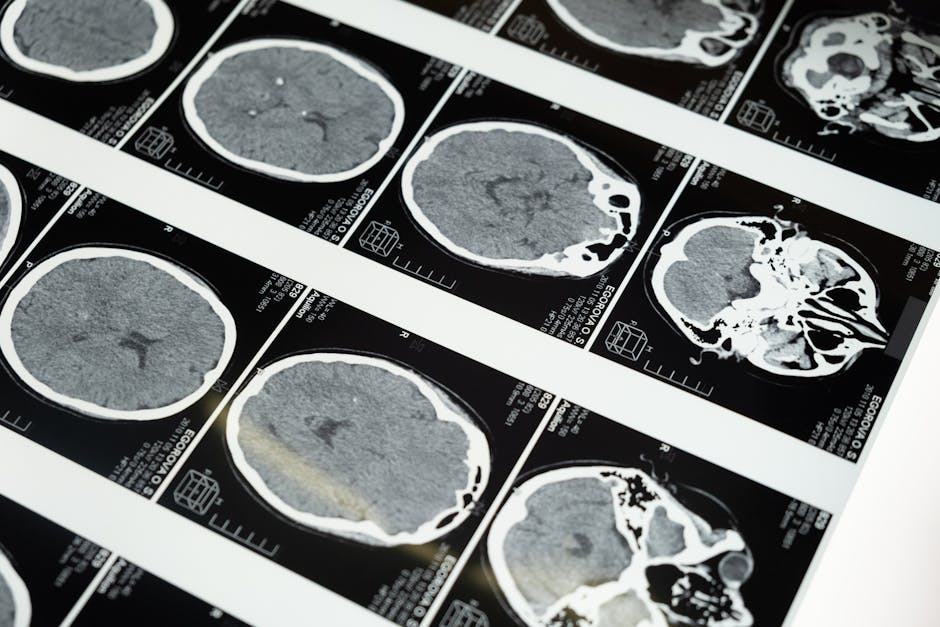

Le radiologue utilise des techniques d'imagerie médicale pour examiner et diagnostiquer les structures internes du corps.

Réalise des examens les plus adaptés en imagerie médicale pour diagnostiquer des maladies et des fractures

Interprète les images médicales pour fournir un diagnostic précis

- Imagerie médicale

- Interprétation des radiographies